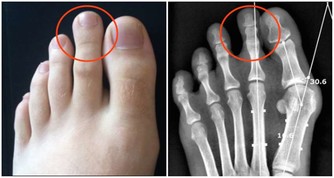

住在中國浙江的一對夫妻,因為工作繁忙的關係而沒時間陪伴10歲的女兒。於是他們買了一隻手機給女兒在無聊時可以打發時間。但有天女兒玩手機玩到一半,聽到媽媽呼喚而抬頭,卻聽到「喀擦」一聲,而且無法動彈,經過醫生的診斷為「頸椎錯位」。

醫生表示,小女孩的頸椎第一、二、三椎向前錯位,「我從醫30多年,第一次碰到這麼嚴重的頸椎病發生在這麼小的孩子身上!」

醫生提醒,人的頸椎就像彈簧一樣,如果常常低著頭,保持同一個姿勢,很容易出現彈性疲乏,而且無法復原,不論大人或小孩,如果經常有,頭暈,頭痛,注意力不集中,甚至噁心想吐著症狀,就有可能是頸椎病變的前兆!